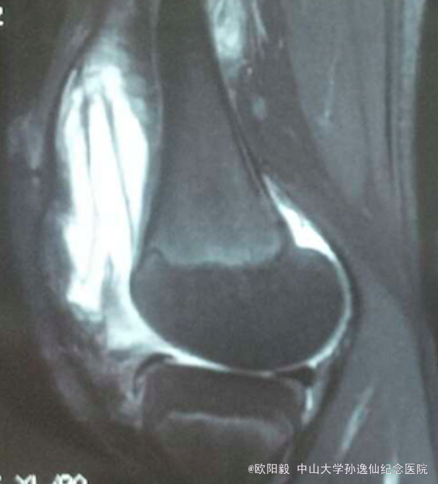

患者女,10岁,因“摔伤致左膝关节反复肿胀1年余”入院。患者1年前摔伤后出现左膝关节肿胀,无明显发热,6个月前曾在外院开放下行左膝滑膜病灶清理术,症状有缓解,但症状仍然反复,余未见明显异常。

查体:左膝关节浮髌征(+),血沉 80,C反应蛋白 15.2,关节液白细胞 41253,余未见明显异常。X线未见明显异常,MRI检查可见髌上囊大量积液。

诊断:左膝关节肿胀查因:感染?拟行左膝关节镜检,病灶清理术。